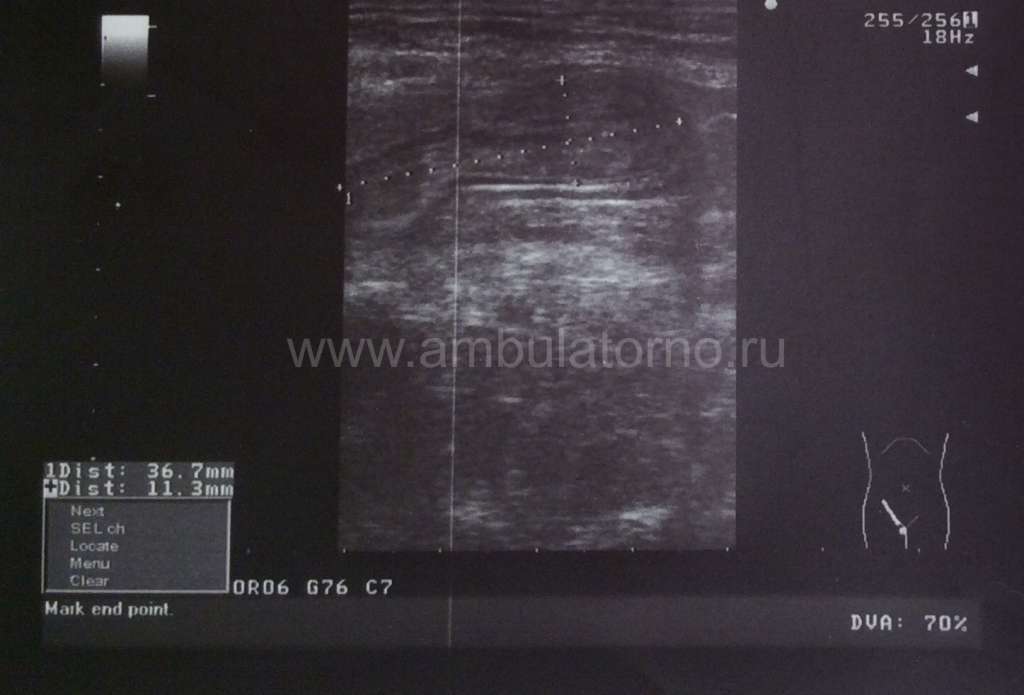

При этом у пациентов с ожирением возможно затруднение при выявлении грыжевого выпячивания. В отдельных случаях это требует проведения дополнительного обследования (УЗИ мягких тканей, МСКТ передней брюшной стенки) с целью подтверждения диагноза либо его исключения.

Если диагноз неясен после медицинского осмотра, ваш врач может назначить визуализационные тесты для проверки на наличие паховой грыжи.Врачи также могут использовать визуализационные тесты для проверки наличия осложнений.

Визуализирующие тесты могут включать